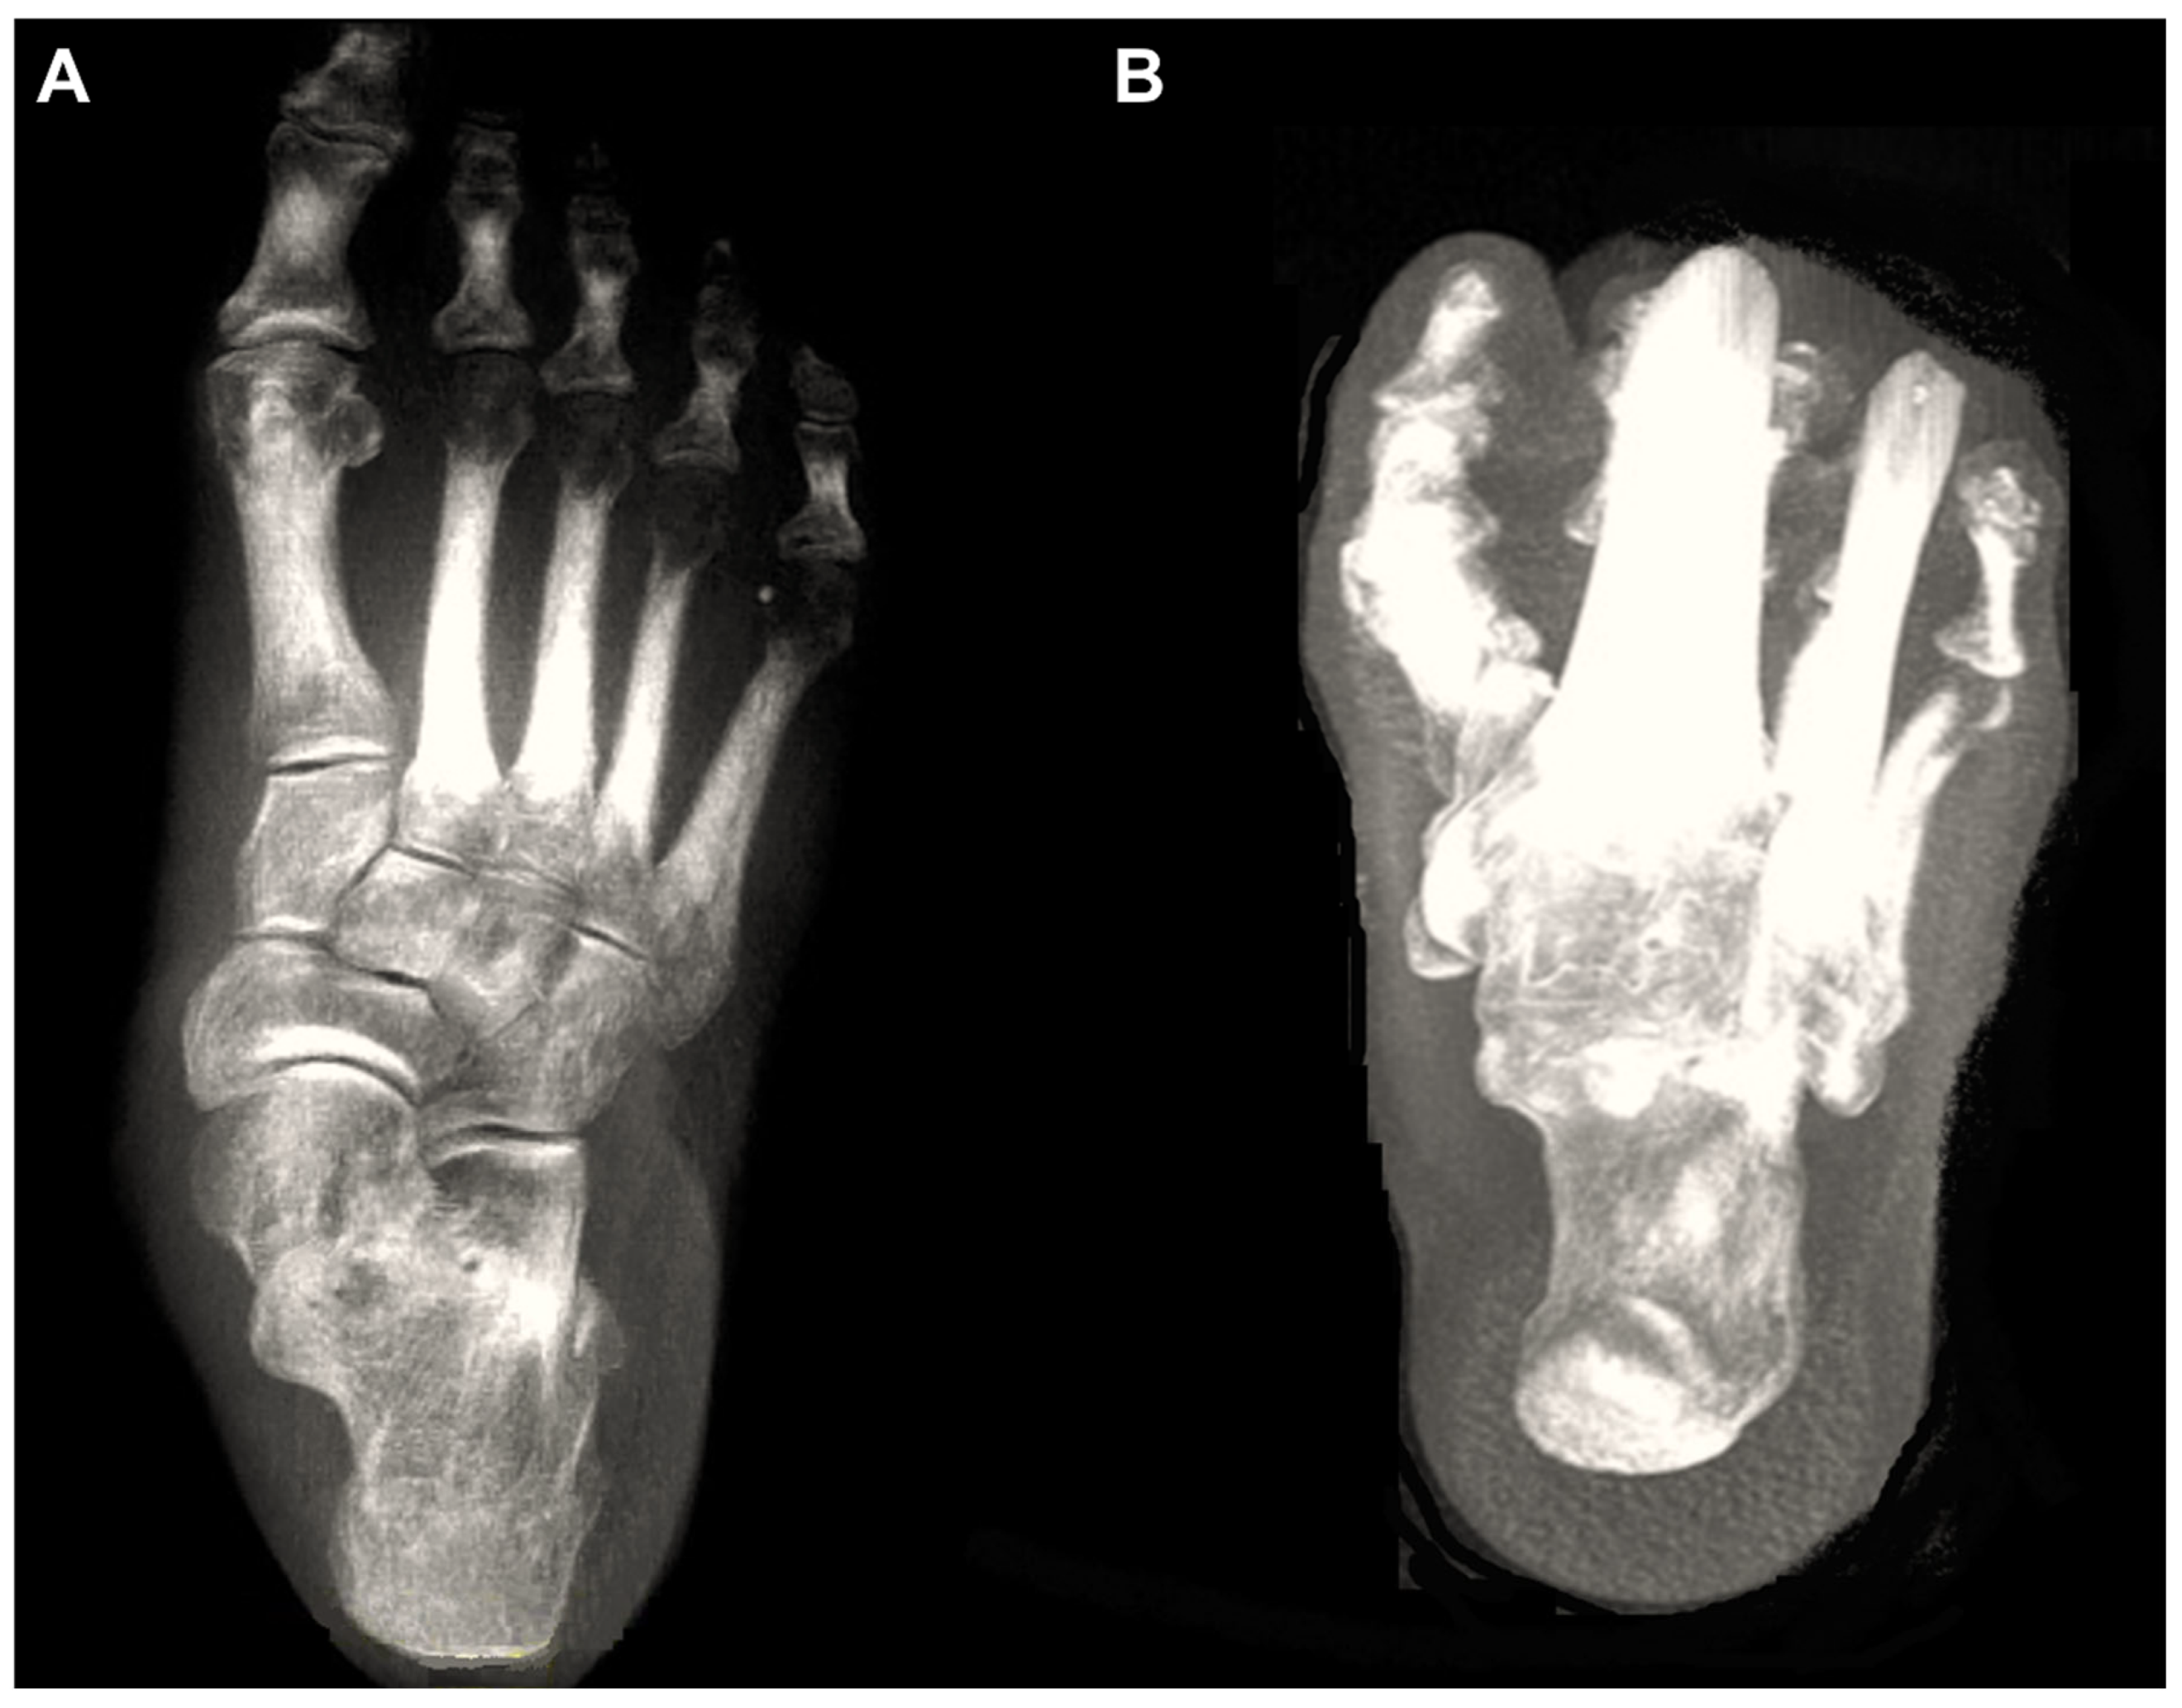

Figure 1. Digitally reconstructed radiographs (DRRs) demonstrating foot anteroposterior (A) and hindfoot alignment (B) views.

Over the past decade, weight-bearing computed tomography (WBCT) has been actively utilized in the field of foot and ankle surgery. In fact, with the development of digitally reconstructed radiographs (DRRs), three-dimensional (3D) processing, and the introduction of artificial intelligence (AI) technologies, WBCT may completely replace conventional radiographs in the near future (Figure 1) [1]. The advantages of WBCT include high accuracy, owing to its 3D imaging that is not affected by bone superimposition or projection angles, low radiation doses, and reduced image acquisition time due to automated processing programs [2].

Figure 6. In the plain radiograph, osteoarthritis of the third tarsometatarsal (TMT) joint is not clearly visible (A); however, weight-bearing computed tomography (WBCT) reveals distinctive joint space narrowing and sclerotic changes (B, C).